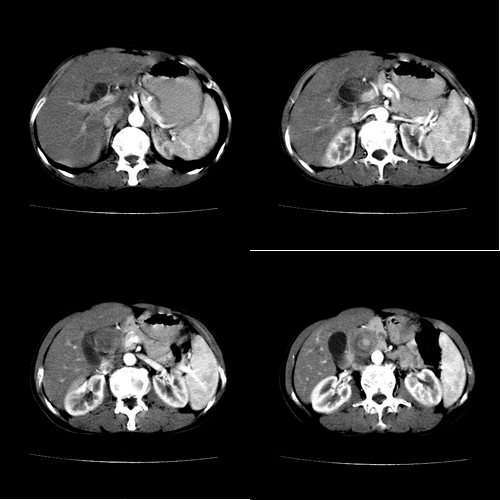

患者 女 60岁,曾多年胆结石及胆管结石,今行ct复查,非常经典.现上传,请讨论.

典型的胆总管铸型结石。

支持胆总管结石。胆囊增大受压,肝内胆管及胰腺管无明显扩张。很有意思的病例,能有冠、矢状重建图像观察就更好了。

相当漂亮的“总胆管(铸型)结石”。多谢楼主!

结石这么大,肝内胆管扩张不明显,胆囊扩张明显。能否考虑结石位于胆囊管内并外压总肝管?

胆总管内多层同心圆样结石,确属精典,谢谢卜一老师!

胆总管铸型结石。